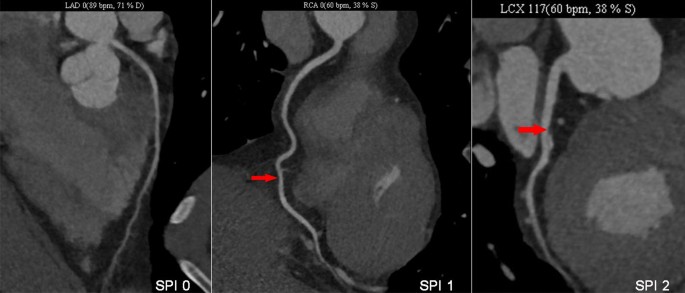

Coronary CTA was performed according to the Society of Cardiovascular Tomography (SCCT) guidelines7 using the following multi-detector CT scanners: Philips Brilliance 64, Philips Medical Systems, Best, the Netherlands; Somatom Definition AS, Siemens Healthineers, Germany. Lesions on coronary CTA were then categorized based on the severity of stenosis: 0% (no CAD) and 1–49% (non-obstructive CAD). Four classifications were defined according to coronary CTA: Traditional NOCAD classification: no CAD (0% stenosis) and NOCAD (1–49% stenosis). NOCAD-RADS classification was defined according to the highest degree of coronary stenosis: NOCAD-RADS 0 (0% stenosis), NOCAD-RADS 1 (1–24% stenosis) and NOCAD-RADS 2 (25–49% stenosis). Duke prognostic NOCAD index: Duke NOCAD 0 (0% stenosis in all vessels), Duke NOCAD 1 (1–24% stenosis, or at most 1 with 25–49% stenosis) and Duke NOCAD 2 (≥ 2 vessels of 25–49% stenosis). Stenosis proximal involvement (SPI) classification: SPI 0 (no CAD, 0% stenosis), SPI 1 (1–49% stenosis with no proximal lesion) and SPI 2 (1–49% stenosis with proximal lesion) (Fig. 2). We defined proximal involvement as any plaque was present (by visual estimation) in the main or proximal segments of coronary artery (left main, left anterior descending artery, left circumflex artery, or right coronary artery).

SPI classification assessed by coronary CTA.